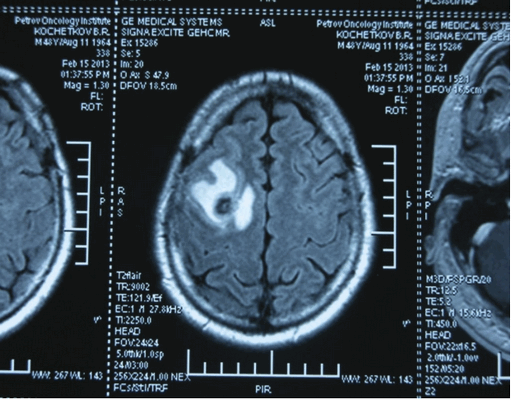

Рисунок 7. - Герминома головного мозга.

Рисунок 9. - метастаз в головной мозг при герминогенной опухоли.

Также выполняют МРТ головного мозга, чтобы выявить наличие метастазов в нем.

![Метастаз в головной мозг при герминогенных опухолях (МРТ головного мозга)]()

Метастаз в головной мозг при герминогенных опухолях (МРТ головного мозга)

Герминогенные опухоли центральной нервной системы (головного мозга) имеют следующие клинические проявления: головная боль, расстройство движений глазных яблок, тошнота, рвота и развитие судорог.